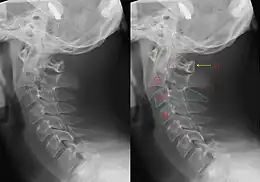

X-ray of the cervical spine with a Hangman's fracture. Left without, right with annotation. It can be seen clearly that C2 (red outline) is moved forward with respect to C3 (blue outline).